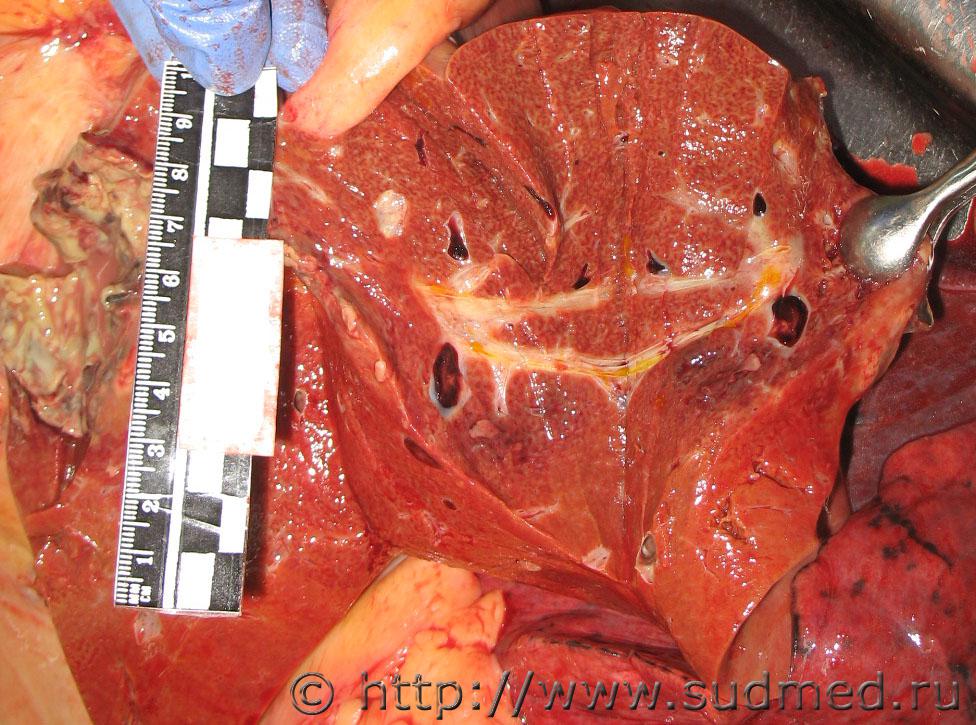

Болезнь и синдром Бадда-Киари.

Болезнь Бадда-Киари - первичный облитерирующий эндофлебит печеночных вен с тромбозом и последующей их окклюзией, а также аномалии развития печеночных вен, ведущие к нарушениям оттока крови из печени.

Синдром Бадда-Киари - обструкция (тромбоз) печеночных вен, которая наблюдается на уровне их впадения в нижнюю полую вену и приводит к нарушению оттока крови из печени. Впервые заболевание было описано английским врачом G. Budd в 1845 г. Позднее, в 1899 г. австрийский патолог Н. Chiari предоставил информацию о 13 случаях этого синдрома. Синдром Бадда-Киари - вторичное нарушение оттока крови из печени, не связанных с изменениями сосудов печени.

Фотоотчет из секционной: болезнь Бадда-Киари.

Судебная медицина - Прикрепленное изображение Судебная медицина - Прикрепленное изображение Судебная медицина - Прикрепленное изображение Судебная медицина - Прикрепленное изображение Судебная медицина - Прикрепленное изображение Судебная медицина - Прикрепленное изображение Судебная медицина - Прикрепленное изображение.